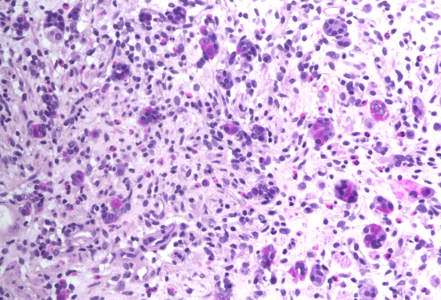

Gastric biopsies from a 68-year-old male with history of lung cancer.

Immune checkpoint inhibitor associated gastritis.

Histology showed an extremely altered gastric mucosa, with architectural distortion by glandular atrophy, degenerative epithelial changes, erosions and an expanded oedematous lamina propria (PANEL A-C). On higher magnification, the lamina propria contained a mixed inflammatory infiltrate, characterized by lymphocytes, plasma cells, eosinophils and neutrophils, focally with abscess formation. We observed withering glands lined by flattened eosinophilic epithelium, occasionally containing apoptotic debris (PANEL D-E); in other areas, little atrophic neuroendocrine nests were found (PANEL F). In summary, there was a severe acute inflammation and signs of acute epithelial injury highly suggestive of a drug-induced gastritis, consistent with injury due to pembrolizumab.